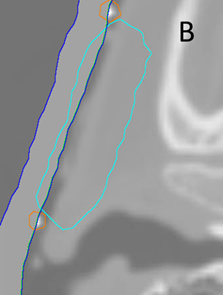

A Planning photo of an elderly man with symptomatic actinic field change anterior to the left pinna that had grown invasive disease. A lesion within the area of concern had been recently excised and found to have a positive deep margin on histopathology. The solid line indicates the CTV. The dotted line indicates the planned electron field.

B Planning axial computed tomography (CT) scan through the volume showing the contour of the planning target volume (PTV) in light blue that was drawn by the RO. Half a centimetre of bolus was used to achieve the full dose to the skin.